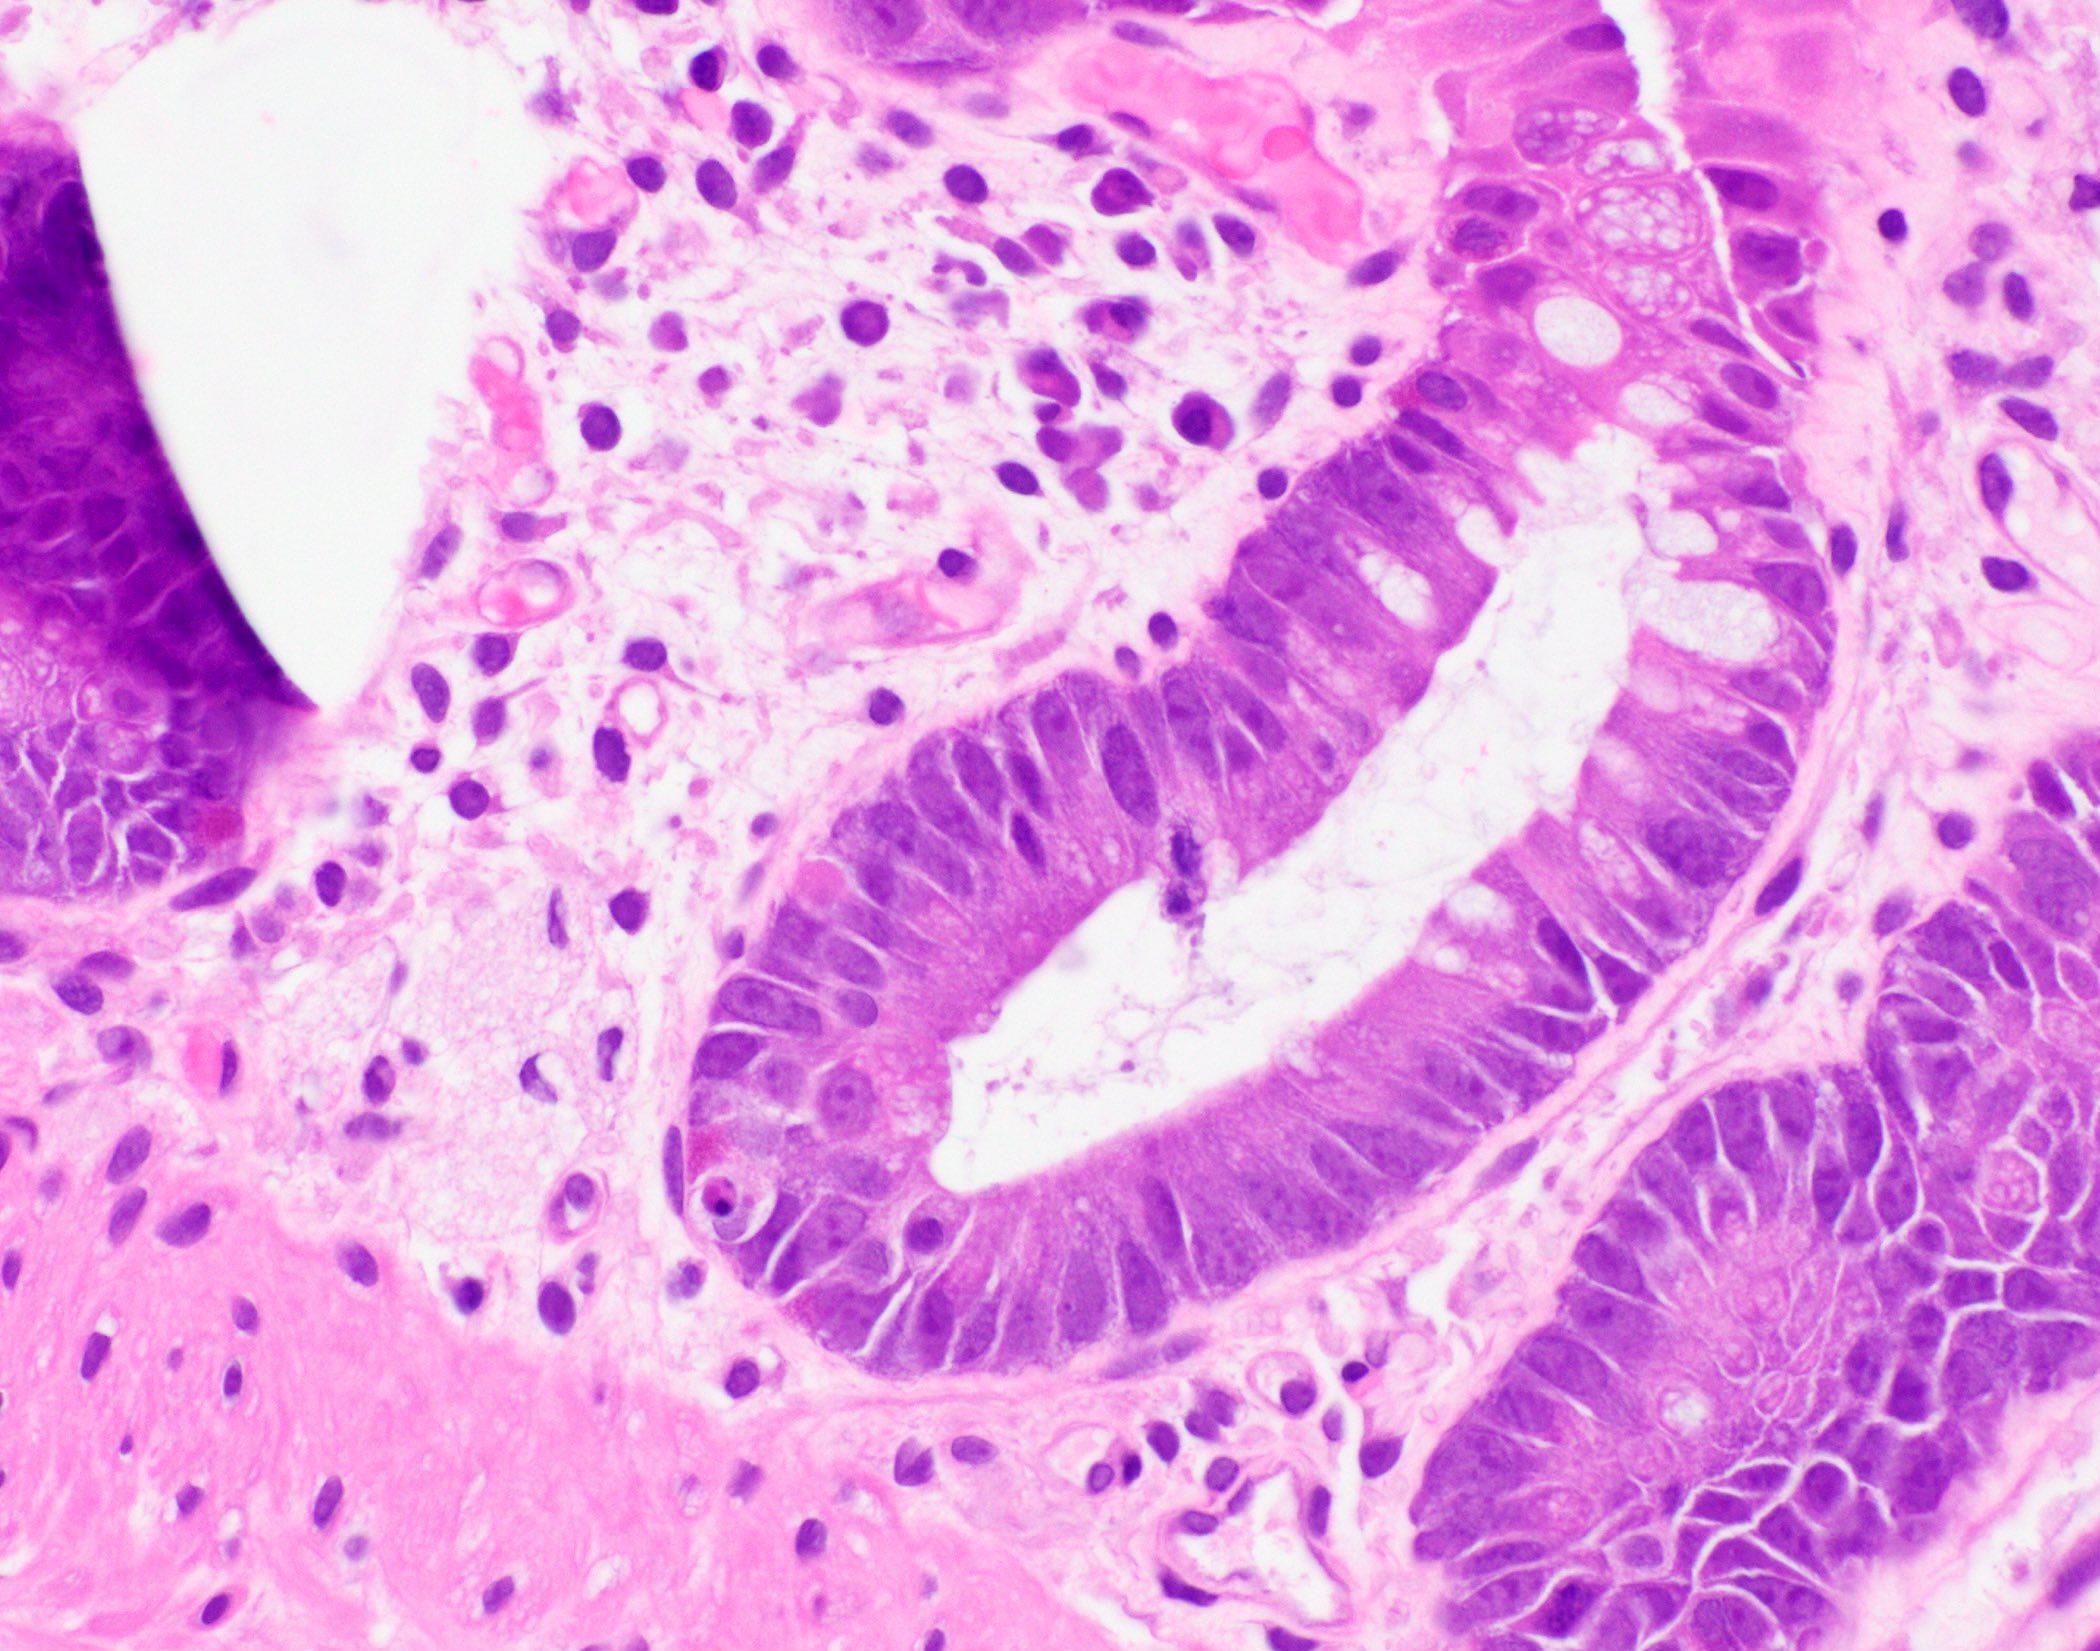

- Characteristic histologic features include crypt apoptosis, crypt dropout and ulceration (Biol Blood Marrow Transplant 2015;21:589)

- Inflammation is generally sparse

- Endocrine cell nests may be seen (Am J Surg Pathol 2013;37:1319)

- Fibrosis and crypt architectural changes are markers of longstanding disease but not specific features of chronic graft versus host disease (Am J Clin Pathol 2016;145:591)

- Apoptosis in the colon is not specific to graft versus host disease and the lower diagnostic threshold is debated

- National Institute of Health proposes ≥ 1 apoptotic body per biopsy fragment (Biol Blood Marrow Transplant 2015;21:589)

- Others propose > 6 apoptotic bodies per 10 contiguous crypts for definitive diagnosis of graft versus host disease (Am J Surg Pathol 2013;37:539)

- Cases with ≤ 6 apoptotic bodies per 10 contiguous crypts are considered indeterminate for graft versus host disease (Histopathology 2016;69:802)

- Utility of histologic grading is questionable because of poor correlation with patient outcome

- When grading is performed, the Lerner system is most commonly utilized

- Grade I: crypt apoptosis without crypt dropout

- Grade II: single crypt dropout

- Grade III: contiguous crypt dropout

- Grade IV: diffuse crypt dropout with ulceration

- When grading is performed, the Lerner system is most commonly utilized

- Graft versus host disease in autologous stem cell transplant patients shows more prominent crypt apoptosis but is otherwise histologically identical to allogeneic graft versus host disease (Mod Pathol 2018;31:1619)

- Histologic examination of at least 8 serial sections is recommended to avoid missing rare apoptotic bodies (Biol Blood Marrow Transplant 2015;21:589)

Microscopic (histologic) images